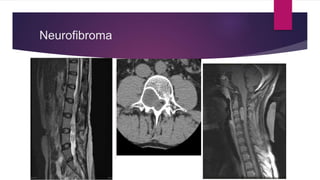

Neurofibroma

 Neurofibroma: Most common NST in young patient & have no

predilection for either sex

Arises from dorsal sensory nerve roots of thoracic spine usually

Not always associated with Neurofibromatosis 1.

Usually painless, slow growing and aymptomatic

Dumbell shaped thoracic neurofibroma represents distinct type of tumour it can involve spinal

canal & thoracic cavity

*Autosomal dominant inherited condition arises from nonmyelinating type schwaan cell that exhibit biallelic

inactivation of NF1 that codes for the protein Neurofibromin which is responsible for regulating RAS mediated cell

growth signalling pathway